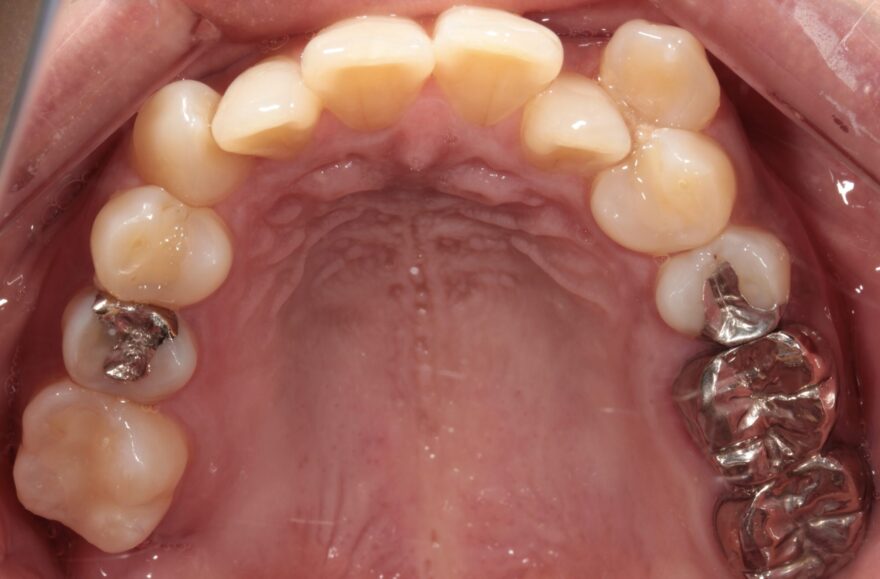

初診時の口腔内写真

左下の奥歯が崩壊しています。

右下の奥歯を失い、噛み合わせが歪んでいることが分かります。

右上の八重歯が気になります。